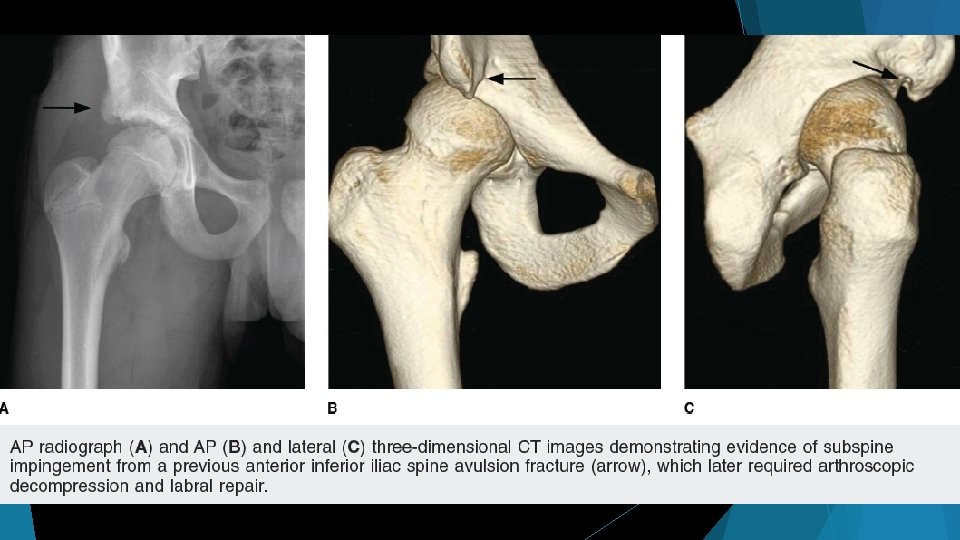

Apophyseal Avulsions Iliopsoas avulsions from ASIS (origin) or lesser trochanter (insertion) Rectus Femoris avulsions from AIIS Hamstring avulsions from ischial tuberosity Adductor avulsions from pubic rami “Post-traumatic” FAI = Subspine Impingement